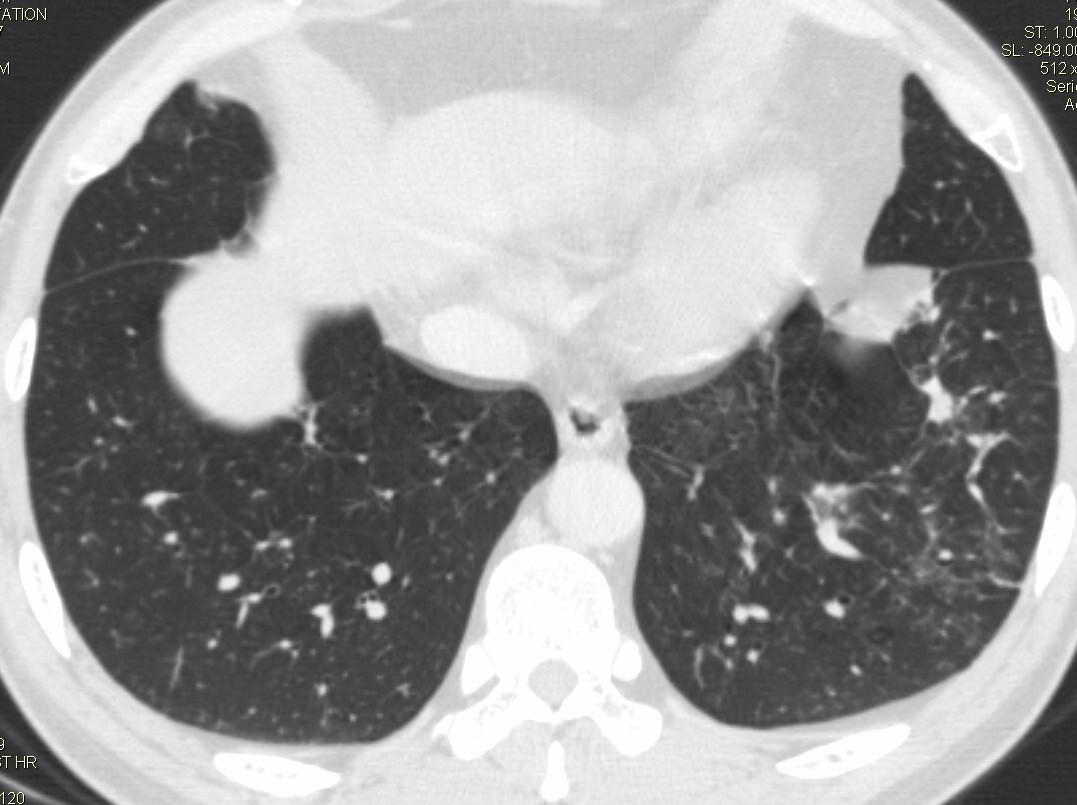

两肺下叶肺纹理增多、增粗并呈“树芽状”改变。支气管扩张呈囊状,部分呈柱状改变。其周围可见散在的斑片样及条索样密度增高影,右肺下叶近叶间胸膜可见一形态不规则的高密度结节影,并与胸膜粘连。

考虑:支扩并发感染。

双肺多发炎性病灶,结核可能性大,建议抗炎治疗复查.右肺下叶前基底段结节灶,高度警惕肺癌可能

双肺间质性改变(间质纤维化?)伴支扩。右肺下叶有毛刺的小结节,考虑周围型肺癌可能性。